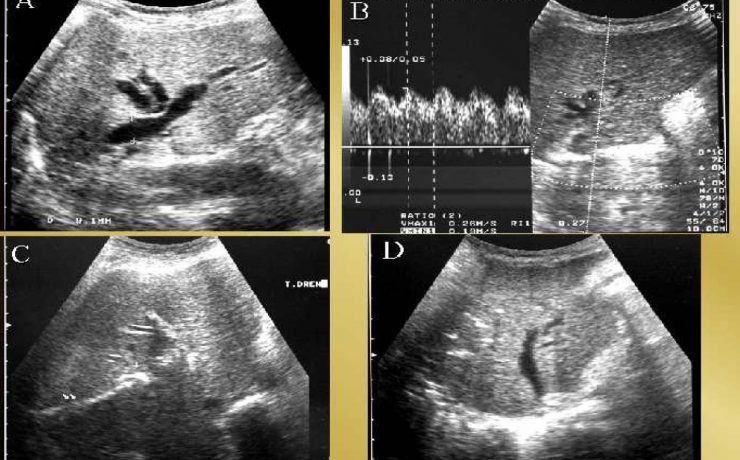

SEGMENTACIÓN HEPÁTICA. EVALUACIÓN ECOGRÁFICA

El hígado se encuentra en el hipocondrio derecho, pesa 1.5 a 2 kg en el adulto y se encuentra mantenido en su posición por la vena cava inferior, las venas suprahepaticas, el ligamento redondo del hígado y los ligamentos coronales y triangulares. Viendo al hígado de manera anterosuperior, se divide